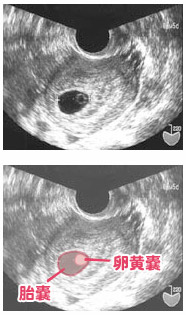

5周4日 胎嚢

妊娠5週4日 5w4d の超音波 エコー 写真

妊娠5週4日 5w4d の超音波 エコー 写真

第3話 5週4日 卵黄嚢が確認できました 胎嚢の大きくなり方物語 妊娠ぱっぴー